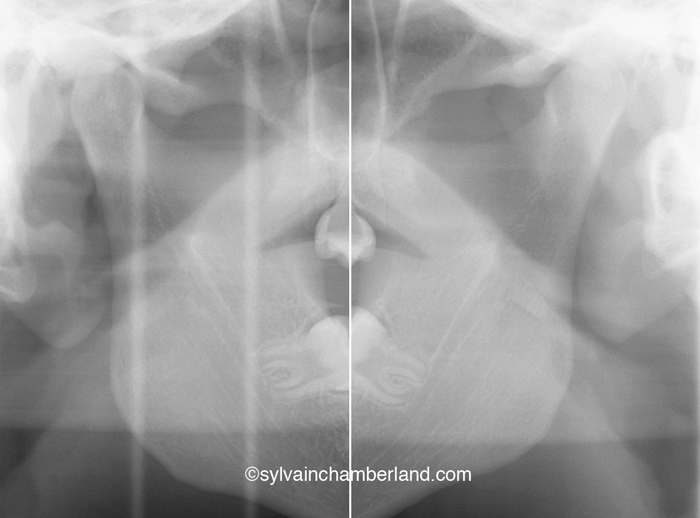

Voici les photos cliniques d’un cas semblable décrit plus haut. La béance antérieure est indiquée par les flèches noires. L’autorotation postérieure est indiquée par la flèche bleue. La résorption du condyle est indiquée par la flèche verte et la résorption de l’éminence est indiquée par la flèche bleue.

1- Il est vrai qu’une résorption condylienne bilatérale comme dans le cas présenté dans la photo de gauche cause une béance antérieure.

5- La radiographie de droite représente l’état des condyles complètement résorbés du cas clinique illustré sur la photo de gauche.

Ce patient a reçu des prothèses totales des 2 articulations temporomandibulaires.

Sur la radiographie de gauche, la plus grande barre horizontale représente la 2e vertèbre cervicale. Normalement, l’angle goniaque est situé à cette hauteur. La résorption des condyles a causé un raccourcissement de la branche montante de sorte que l’angle goniaque se trouve à hauteur de la 1re vertèbre cervicale. La petite barre horizontale indique la largeur du tractus oropharyngé. il faut avoir normalement 10 à 15 mm. Dans ce cas, il y a à peine 5 mm de largeur.